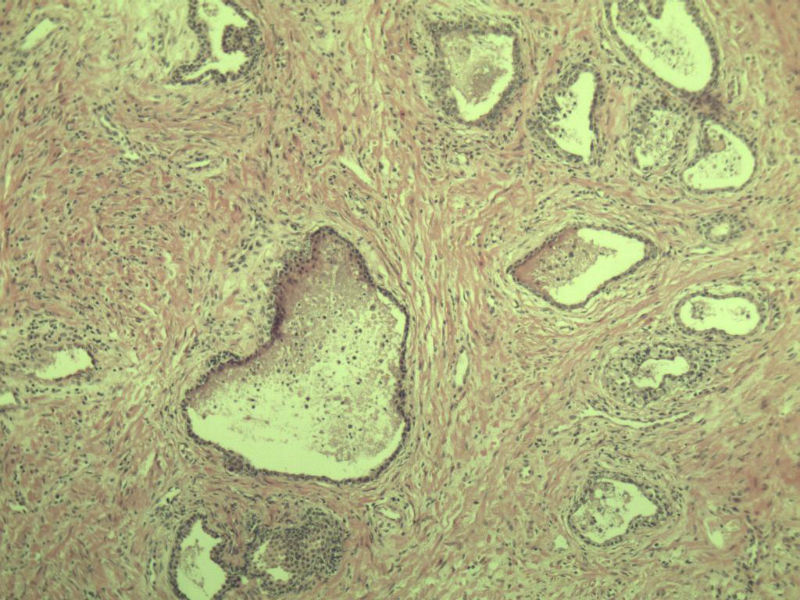

男 75岁 因排尿困难半年行前列腺切除术,体积 4 × 3 × 2.5 cm3,切面灰白,实性,质韧。请各位老师看看 有问题没? 谢谢了!

高级别上皮内瘤变,建议免疫组化:P63、34BE12、P504S

前列腺增生症伴鳞化

良性前列腺增生伴尿路上皮化生

呈巢上皮为尿道周围前列腺组织正常现象。尿路上皮-前列腺腺体过度。

良性。

良性前列腺增生伴brunnerr巢形成

前列腺增生伴尿路上皮鳞化及Brown巢形成,未见恶性。